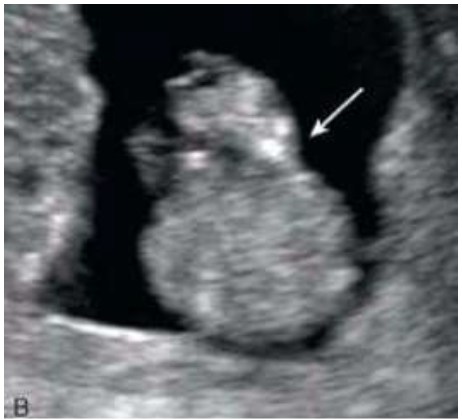

Em relação a malformação da parede abdominal e do trato gastrointestinal fetal, assinale a alternativa correta: